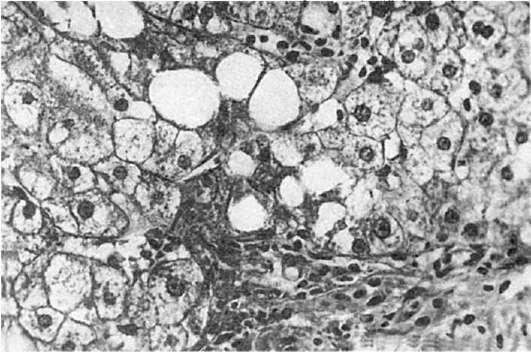

Рис.

218. Хронический персистирующий алкогольный гепатит (биопсия печени). Ожирение гепатоцитов, склероз и лимфогистиоцитарная инфильтрация стромы портальных трактов